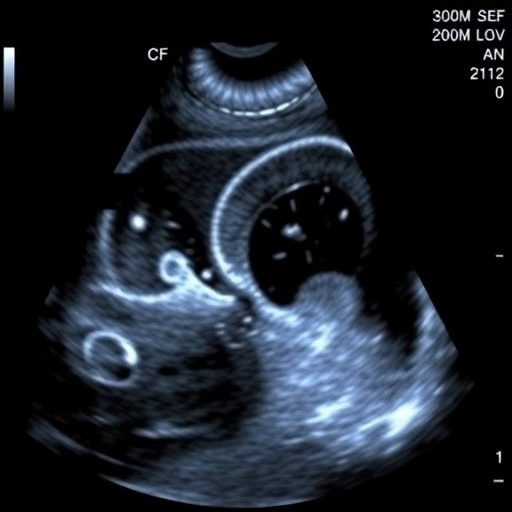

To address this diagnostic blind spot, supplemental ultrasound has been proposed as a complementary tool alongside mammography. Ultrasonography offers the advantage of differentiating dense tissue textures and detecting lesions that mammograms may miss. Despite its theoretical benefits, the incorporation of additional ultrasound into national public screening programs remains fraught with uncertainty regarding its feasibility and acceptance among both healthcare providers and screening clients.